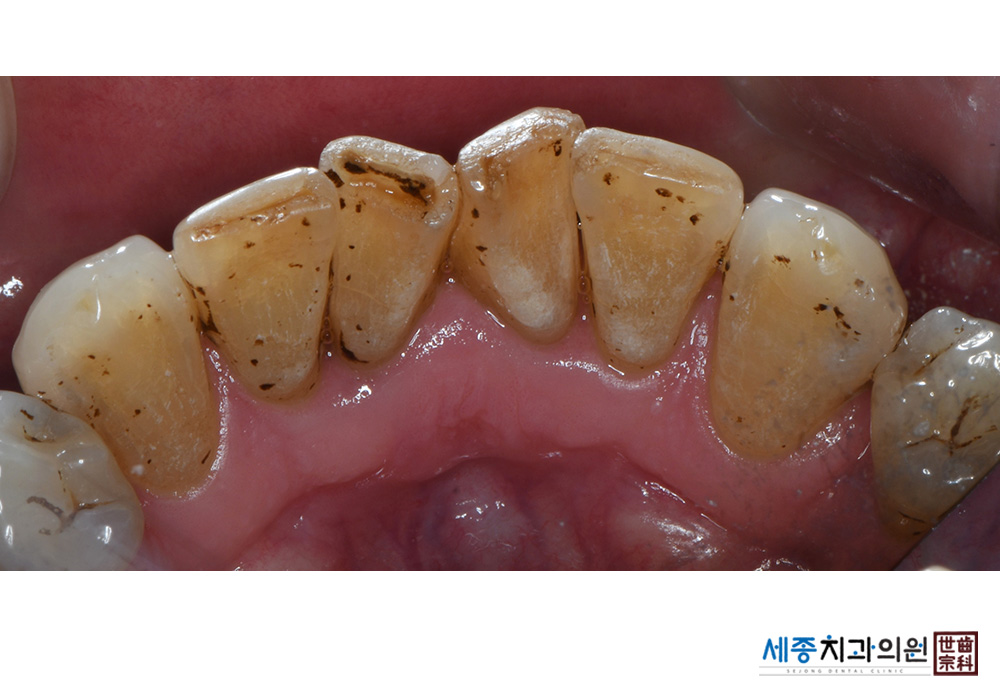

[스케일링] 치주질환 예방 스케일링

치료전 : 2021-02-01

치료후 : 2021-02-01

가글마취&저주파 스켈러를 사용한 스케일링